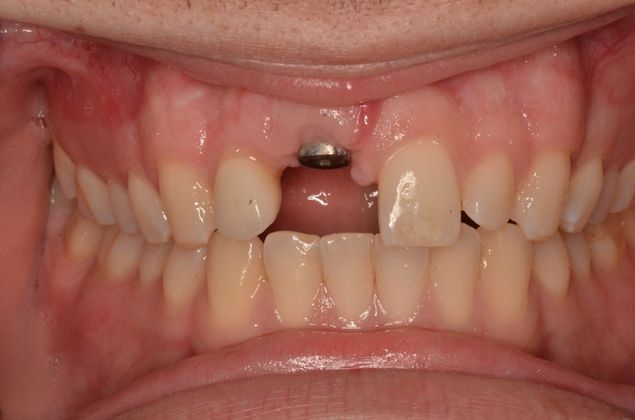

Replacing a missing upper central with an implant and a screw retained implant crown